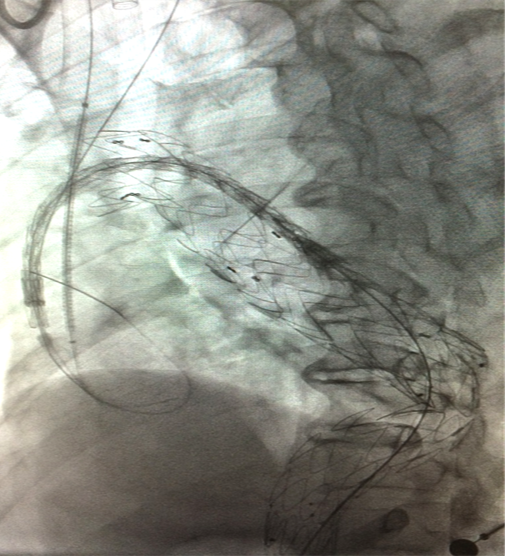

男, 49岁,急性夹层 。2018年11月TEVAR。一月后复查:RTAD 。 2019年1月双开窗。2019年4月2日 复查,结果良好。

▎病例五

男,49岁,急性AD。2019年1月TEVAR,3月RTAD,行全弓置换+支架象鼻。2022 年1月25日术后复查,结果良好。